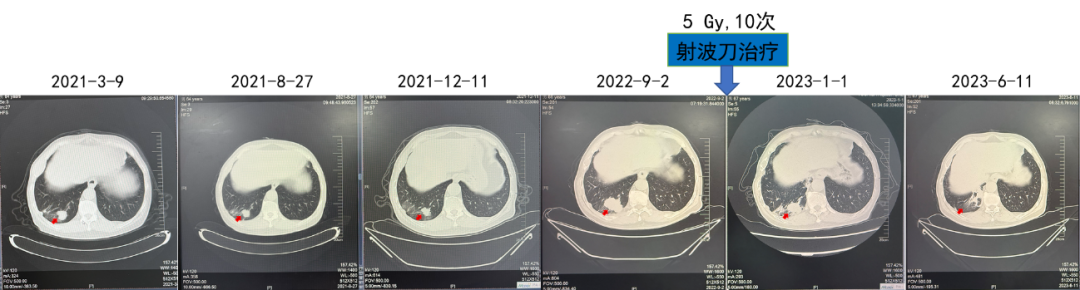

第三阶段:靶免联合+射波刀

2021.03阿昔替尼5mg BD+帕博利珠单抗200 mg+射波刀

疗效:肺部病灶疾病稳定(4年)。对侧肾上腺病灶部分缓解(4年)。

(射波刀治疗)

该例患者诊断为左肾透明细胞癌,T2N0M0,术后5.5年复发,伴肋骨转移、肺转移和胸壁转移。结合循证医学证据及中国临床肿瘤学会(CSCO)肾癌诊疗指南对低危患者推荐,优先使用舒尼替尼进行一线治疗,患者出现不耐受情况,调整剂量后肺部病灶获得部分缓解,肋骨病灶疾病稳定,PFS 2年。后续进展可考虑其他治疗方案。

此外,CheckMate 214研究随访42个月的结果显示,对于IMDC低危人群,舒尼替尼的ORR(54%vs.29%)、中位PFS(27.7个月vs.17.8个月)和42个月OS率(73%vs.70%)均优于双免治疗方案。KEYNOTE-426研究也表明,TKI单药疗效与免疫联合TKI相当,组间差异性并不明显。因而,舒尼替尼成为该例患者的优选方案之一。事实也证明,舒尼替尼单药治疗能够使患者的肋骨肿瘤实现SD,同时肺部病灶获得PR。

由于患者中间治疗停滞一年,可能导致了肿瘤的进一步发展,因而需要针对对侧肾上腺肿瘤进行治疗。对于一线TKI单药治疗后进展的患者,目前多推荐更改为以ICI为基础的靶免联合治疗方案。而对于靶免联合治疗后进展的患者,需要充分考虑患者危险因素与危险分层、药物疗效与耐受性,综合选择治疗方案。